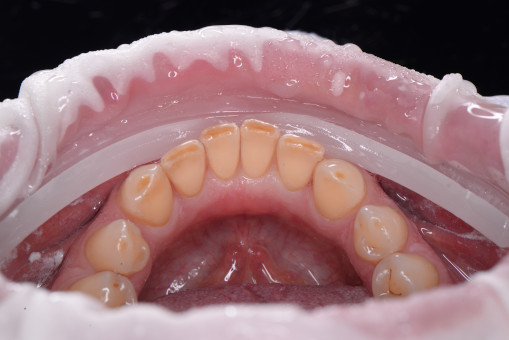

А прежде, чем вы посмотрите фотографии «до» и «после» лечения слизистой оболочки полости рта, проведенных в нашей клинике, хочу поблагодарить большое количество наших пациентов, которые поверили, прониклись нашей концепцией, и мы вместе, именно вместе победили болезни десны, гингивит и пародонтит!

До/после лечения